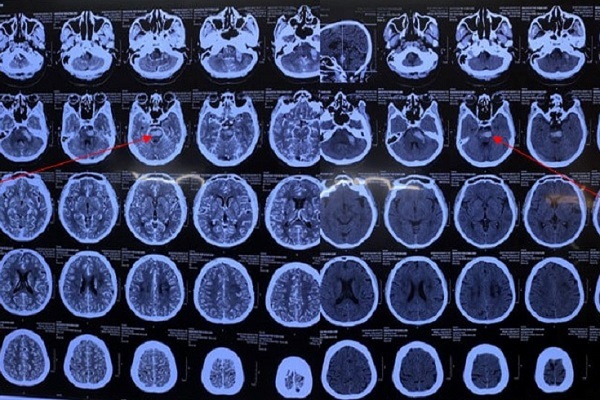

Một tháng nỗ lực cứu bệnh nhân Covid-19 đột quỵ nguy kịch

Bệnh nhân mắc Covid-19 kèm đột quỵ chảy máu thân não; lại là người bệnh cao tuổi, béo phì nên quá trình điều trị gặp không ít khó khăn.